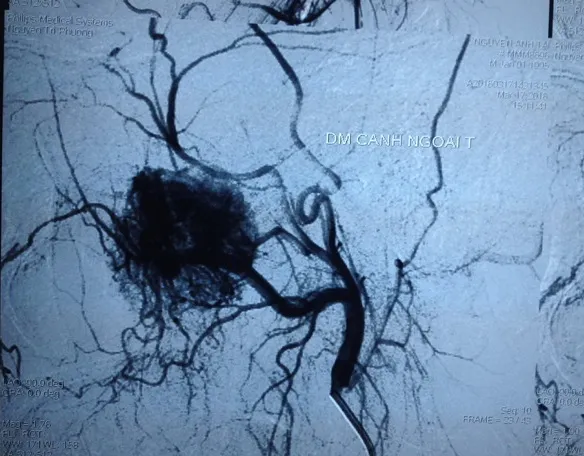

Hệ thống mạch máu khá phong phú của u sợi mạch vòm mũi họng khiến bệnh nhân rất dễ chảy máu.

Chụp mạch máu kỹ thuật số hóa xóa nền cho thấy u có hệ thống mạch máu phong phú. Đây là u sợi mạch rất dễ chảy máu. Bệnh nhân đã được phẫu thuật nội soi qua mũi để cắt toàn bộ khối u.